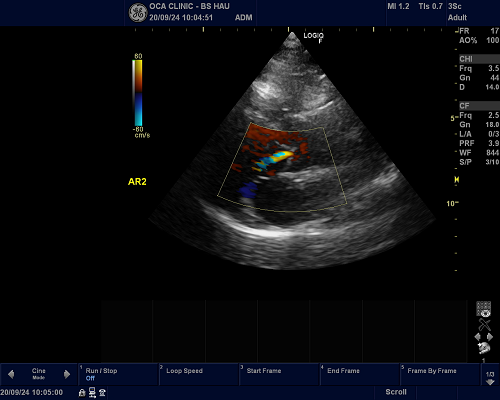

Siêu âm Doppler tim màu là một phương pháp kỹ thuật y học tiên tiến giúp chẩn đoán chính xác bệnh lý liên quan đến tim. Tại phòng khám tim mạch OCA, BS Phạm Xuân Hậu với nhiều năm kinh nghiệm trong lĩnh vực tim mạch sẽ trực tiếp thực hiện thăm khám siêu âm Doppler tim, đảm bảo kết quả chính xác.

• Sử dụng Doppler màu: Để đánh giá hướng và tốc độ máu chảy qua các buồng tim và van tim.

• Các cấu trúc cần đánh giá: Các buồng tim, van tim, và mạch máu lớn.

• Nhận diện dấu hiệu của bệnh: Như hở/hẹp van tim hoặc các bất thường bẩm sinh.

Siêu âm Doppler tim màu là phương pháp hiệu quả để đánh giá chính xác bệnh lý tim. Với kinh nghiệm chuyên sâu, BS Phạm Xuân Hậu sẽ giúp bệnh nhân chẩn đoán sớm các dấu hiệu thiếu máu cơ tim và các bệnh lý liên quan khác. Điều này sẽ giúp bệnh nhân yên tâm hơn và có biện pháp điều trị kịp thời, hạn chế biến chứng.